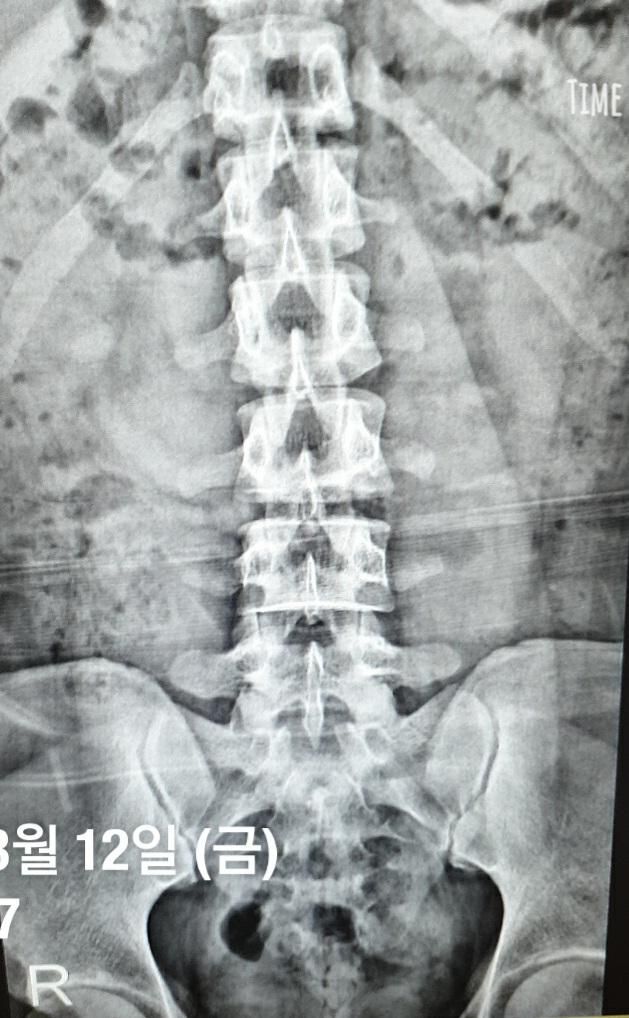

우연히 발견한 과거 허리 X-ray 사진으로 알 수 있는 게 있을까요? 단순한 정면 X-ray 사진만으로 허리 상태가 어떤 지

추측 해볼 만한 게 있는지 궁금합니다.